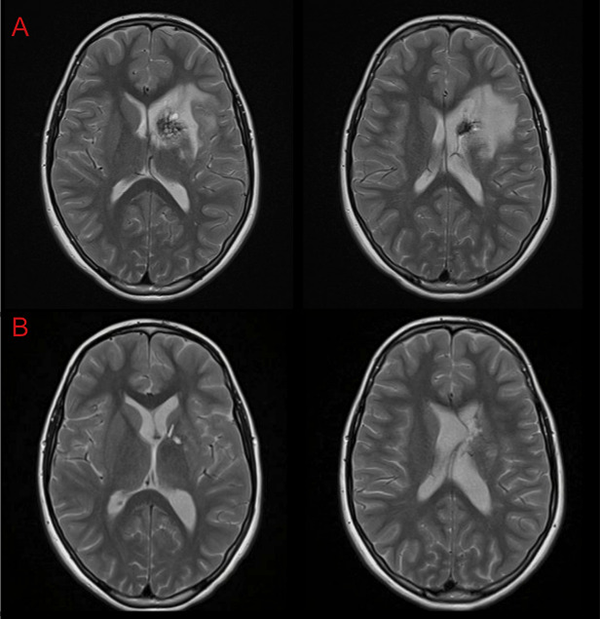

La paciente de 12 años presentó cefaleas, hemiparesia y pérdida de conciencia aguda que requirió soporte de Asistencia Respiratoria Mecánica durante tres días, dos meses previos a la cirugía. Debido al volcado ventricular se colocó un Drenaje Ventricular al exterior. Luego del episodio agudo la paciente se recuperó sin déficit motor. Mediante Resonancia Magnética por Imágenes (RMI) se diagnosticó un Cavernoma adyacente a la CI y sobre el Núcleo Caudado (NC) (Figura 1 A, B y C). El estudio de la RMI por Tensor de Difusión (Tractografía) expuso que la vía motora izquierda no estaba interrumpida completamente, quizá desplazada hacia lateral respecto de la rodilla de la CI (Figura 2).

Otra vía considerada fue el abordaje transfrontal mediante el uso de la técnica “tubular”7 o mediante corticotomía; ambas permitirían acceder al Cavernoma en forma directa pero con la posibilidad de no abarcarlo en su totalidad o incidir inadvertidamente las fibras de la CI. Aunque la elocuencia del tejido a nivel frontal es menor y toleraría mejor las maniobras de retracción necesarias, consideramos que ese corredor quirúrgico también sería estrecho. Nos inclinamos por la vía interhemisférica contralateral por considerar que el sangrado previo según se evidencia en la RMI (Figura 6) había delineado una vía de acceso que evitaría realizar una nueva incisión sobre el tejido sano interpuesto.

Figura 6: RMI A- Preoperatoria. B- Control posoperatorio a las 24hs.